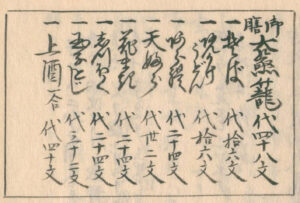

京城帝大大澤博士創製ニカヽル「モクソール」ノ發表ヲ知ル。「モクソール」トハ濃厚ナル酸又ハ「アルカリ」ノ如キ腐蝕劑或ハ寒冷及ビ熱ニ依ツテ惹起セラル、局所障碍ニヨリ生産スル毒素「ヒストトキシン」ノ一 定量ヲ含ムリンゲル氏溶液ナリ。氏ニヨレバ酸及ビ「アルカリ」ノ如キ腐蝕毒ガ組織ニ働クトキハ其ノ作用セシ局所ニ於テ一種ノ藥理學的能動性アル物質ノ産出セラルヽ事ヲ證明セラレ、カヽル物質ハ各方面ヨリ種々研究ノ結果化學的ニハ「ヒスタミン」ニ近似セルモ、生物學的乃至藥理學的性質ハ明カニ相違セルモノナル事ヲ證シ、「ヒストトキシン」ナル名稱ヲ附セラレタリ。

磯部濶. 日本消化機病学会雑誌, 1935